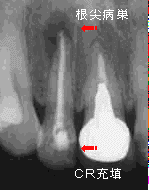

主訴の4|は、根管治療後の歯でパノラマ写真では明瞭な根尖病巣が確認できた。

クラウンおよびポストコアー除去後、通法に従って根管清掃を行い、出血や排膿がないことを 確認して即日充填を行った。翌日まで若干の疼痛が認められたものの、術後の経過は良好で、 根尖病巣部に存在した漏孔も1週間後には閉鎖。再びメタルコアーによる支台形成を行い、 最終補綴物を装着して同部の治療を終了した。

私の医院では、根尖部からの出血や排膿がない限り即日充填を基本としています。 根尖病巣の原因は、根管内に貯留した汚物に対するアレルギー反応に呼応したように 発生する根尖部の炎症です。原因となる汚物を機械的に(可及的)完全除去し、再び汚物が 貯留しないように死腔を(可及的)完全閉鎖すれば、根尖部の炎症は治まり破壊された 骨組織も根尖病巣の大きさに関係なく再生されます。